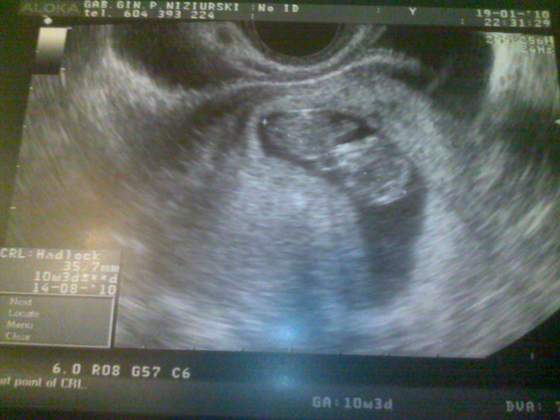

Jejku, jak wyraźnie widać.. jakie piękne maleństwoA mi wkoncu lekarz przyslal oczekiwane usg z poprzedniej wizyty.

Wiec wrzucam moja zabke:-) Tak wygladala tydzien temu![]()